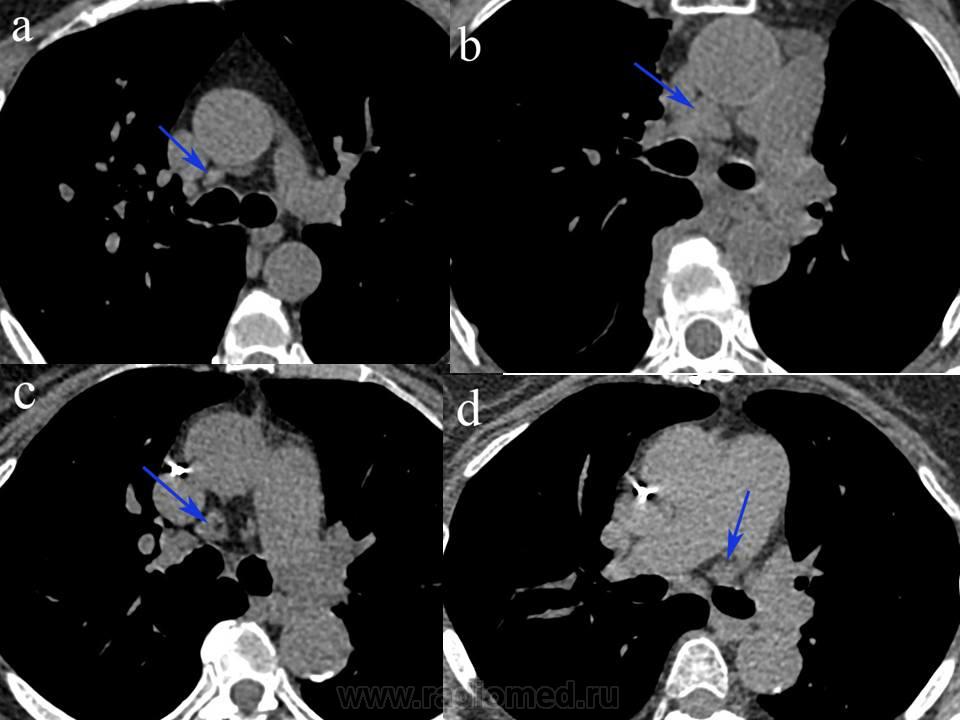

Очень интересует мнение коллег. Как вы считаете, к какой  группе  принадлежат  эти лимфоузлы? (расположены сразу ниже уровня бифуркации, у передней стенки главных бронхов) -  название группы, номер группы по классификациям  Mountain 1997   и  IASLC 2009.

Возможно, совсем маленькая надежда на это была, а в целом - просто хотелось услышать мнение разных рентгенологов. Я сам работаю в торакальном центре, и вот, вдруг заметил, что у нас (рентгенологов) нет единого мнения по этому вопросу. У торакальных хирургов тоже нет однозначного решения, они все знают классификацию Mountain, про последний вариант  классификации 2009г - скорее что-то слышали, хотя именно по ней в основном и мыслят. А те самые узлы, которые я отметил стрелкой, часть специалистов (рентгенологи, эндоскописты и хирурги)вообще  назвали бифуркационными.

Различие именно между MD-ATS и IASLC классификациями в отношении 4 и 10 групп лимфоузлов (посмотрите на картинки). Например в приведенном в первом посте случае d - лимфоузел был бы 4L группы по MD-ATS , но по IASLC он 10 уровня. (корневой). Если бы было стадирование то разница была бы в целую стадию (не II а Ш), так как 4  = это уже N2.

Различия между японской класиификацией (NARUTO) и ISLC тоже хватает. Непосредственно в отношении лимфоузлов это приведенные выше 7 и 10 уровни.

Обвел слева л/у, который якобы не расположен в средостении, но группа  N10.

И цитата: "10. Hilar nodes

These include nodes adjacent to the main stem bronchus and hilar vessels.

On the right they extend from the lower rim of the azygos vein to the interlobar region.

On the left from the upper rim of the pulmonary artery to the interlobar region".

Как они могут быть вне средостения, и в тоже время по ходу главных бронхов? Ответ: никак. Здесь ключевая фраза "...These include nodes adjacent to the main stem bronchus and hilar vessels".

Из другого: "Hilar lymph nodes are those that are immediately adjacent to the main-stem bronchus and hilar vessels, including the proximal portions of the pulmonary veins and main pulmonary artery". Проксимальная порция ЛА располагается в т.ч. и в средостении.